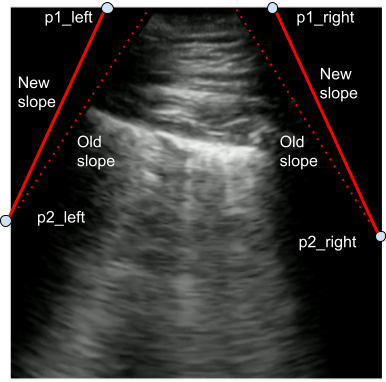

If the bounds of the viewing window is known, then the POCUS image can be transformed to have various different angles by remapping the corners of the viewing window via a random projective transform. This process is shown in Figure 2. Furthermore, we transform the POCUS images captured using linear probes using random projective transforms so that they bare a much stronger visual resemblance to POCUS images captured using a convex probe to enable the deep neural network to better leverage this additional data source. An example of this POCUS augmentation is shown in Figure 3a and Figure 3b.

The models are trained with no additional data augmentation techniques. Projective image transformations are set with a slope sampled from a normal distribution centered around either the original slope for convex images or 2.5 for linear images, and a standard deviation of 0.15.